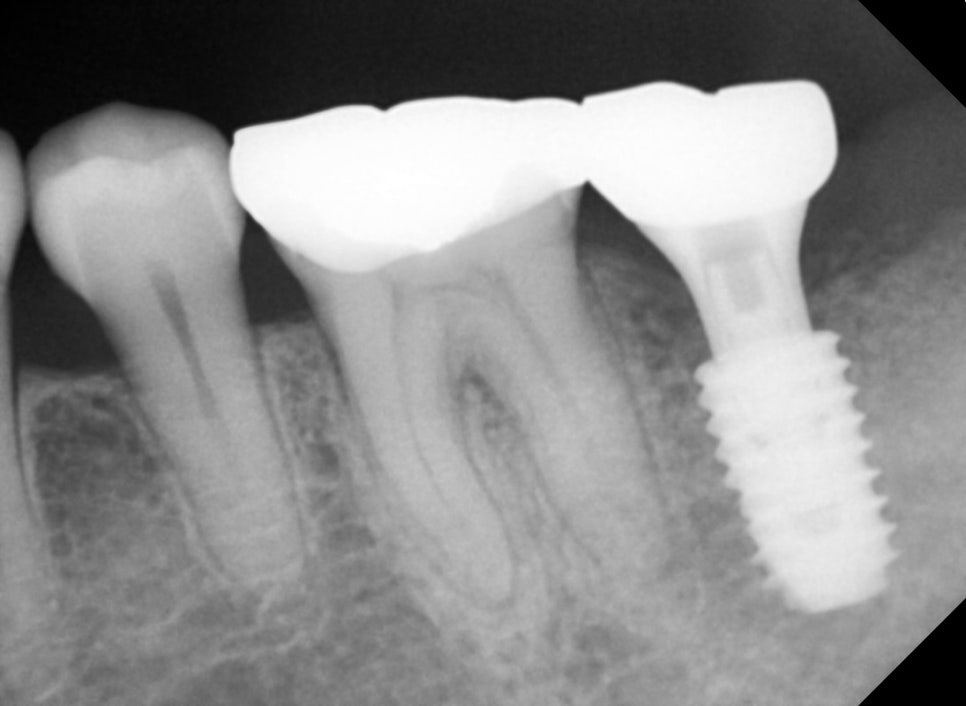

Recovery and second surgery process

After implant placement, time is needed for the bone and implant to

integrate.

After about 2 to 3 months, a second surgery is performed

to connect the implant above the gums.

Important prosthetic treatment for molar implants

The completion of implant treatment is determined at the prosthetic stage.

In this case,

custom abutment applied

zirconia prosthesis fabricated

occlusal adjustment

were performed.

Because molar implants must withstand chewing force,

accurate occlusion is very important.

Even the slightest occlusal differences are adjusted to ensure stability.